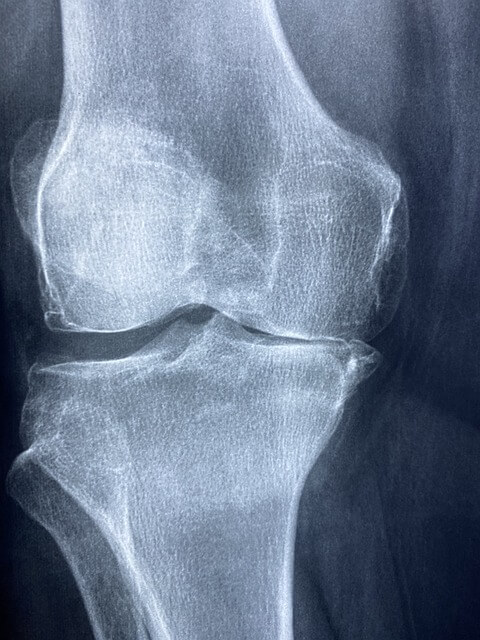

1. 관절 건강 증진: 콘드로이친은 연골의 구성 성분으로, 관절 강직과 손상을 막는 데 도움 됩니다. 또한 연골 조직의 천연 스펀지 역할을 해 원활한 관절 움직임에 기여하며 관절 내 충격 흡수능을 증진시킵니다.

2. 연골 손상 예방: 콘드로이친은 인체 내에서 연골의 탄력을 높이고 주기적인 새로운 세포 생성을 도와 손상된 연골을 회복시키며 추후 손상을 예방하는 데 도움이 됩니다.

3. 관절염 증상 완화: 콘드로이친이 관절 염증과 통증을 줄이는데 도움을 주며 특히 고관절염, 무릎관절염 등 관절염 환자에게 효과적입니다. 글루코사민과 함께 사용하면 더욱 효과적인 증상 완화가 기대됩니다.

4. 통증 감소: 콘드로이친 복용으로 인한 통증 완화 효과가 뚜렷한 것으로 알려져 있습니다. 수술 못지않은 효과를 거둔 예도 있습니다.

5. 관절 윤활제 생성 촉진: 콘드로이친은 인체에서 자연으로 생성되는 관절 윤활제의 생성을 촉진하며 연골과 뼈 마모를 줄이고 관절의 원활한 움직임을 지원합니다.

6. 연골 재생: 노화로 인한 연골 손상이 증가할 수 있으나 콘드로이친을 섭취해 나이가 들어도 연골의 손상을 줄이고 건강한 관절 상태를 유지할 수 있습니다.